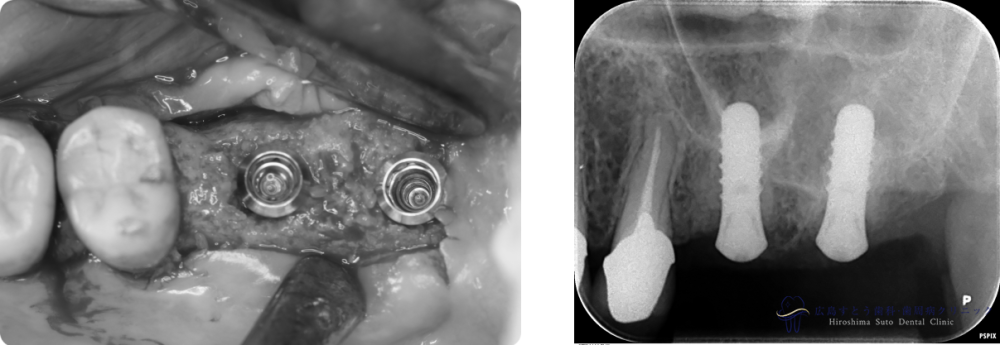

インプラント手術時

インプラント手術中

手術直後のレントゲン

6ヶ月後のレントゲン写真